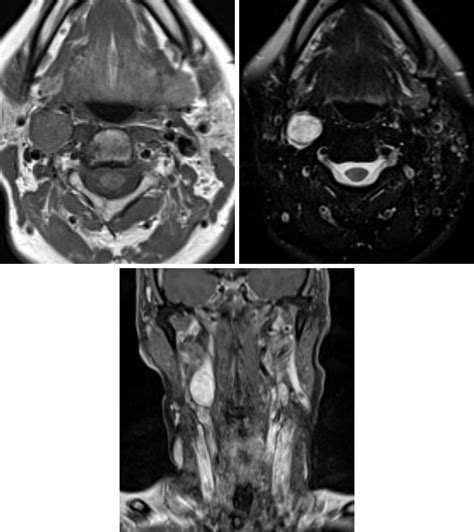

• Imaging studies: Various imaging techniques are used to visualize the tumor and determine its size, location, and extent. Common imaging studies include:

Magnetic Resonance Imaging (MRI) Offers high-resolution images of soft tissues and can help differentiate the tumor from surrounding structures.